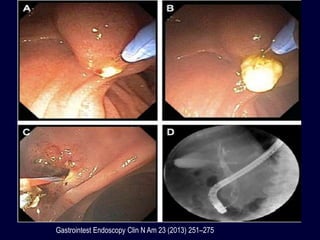

Gastrointest Endoscopy Clin N Am 23 (2013) 251–275

PRECORTE

• Utilidad en el 85% de casos en los que

había fallado la técnica convencional

• Pacientes con Billroth II

• Abordaje con corte hacia el meato papilar

• Fistulotomía